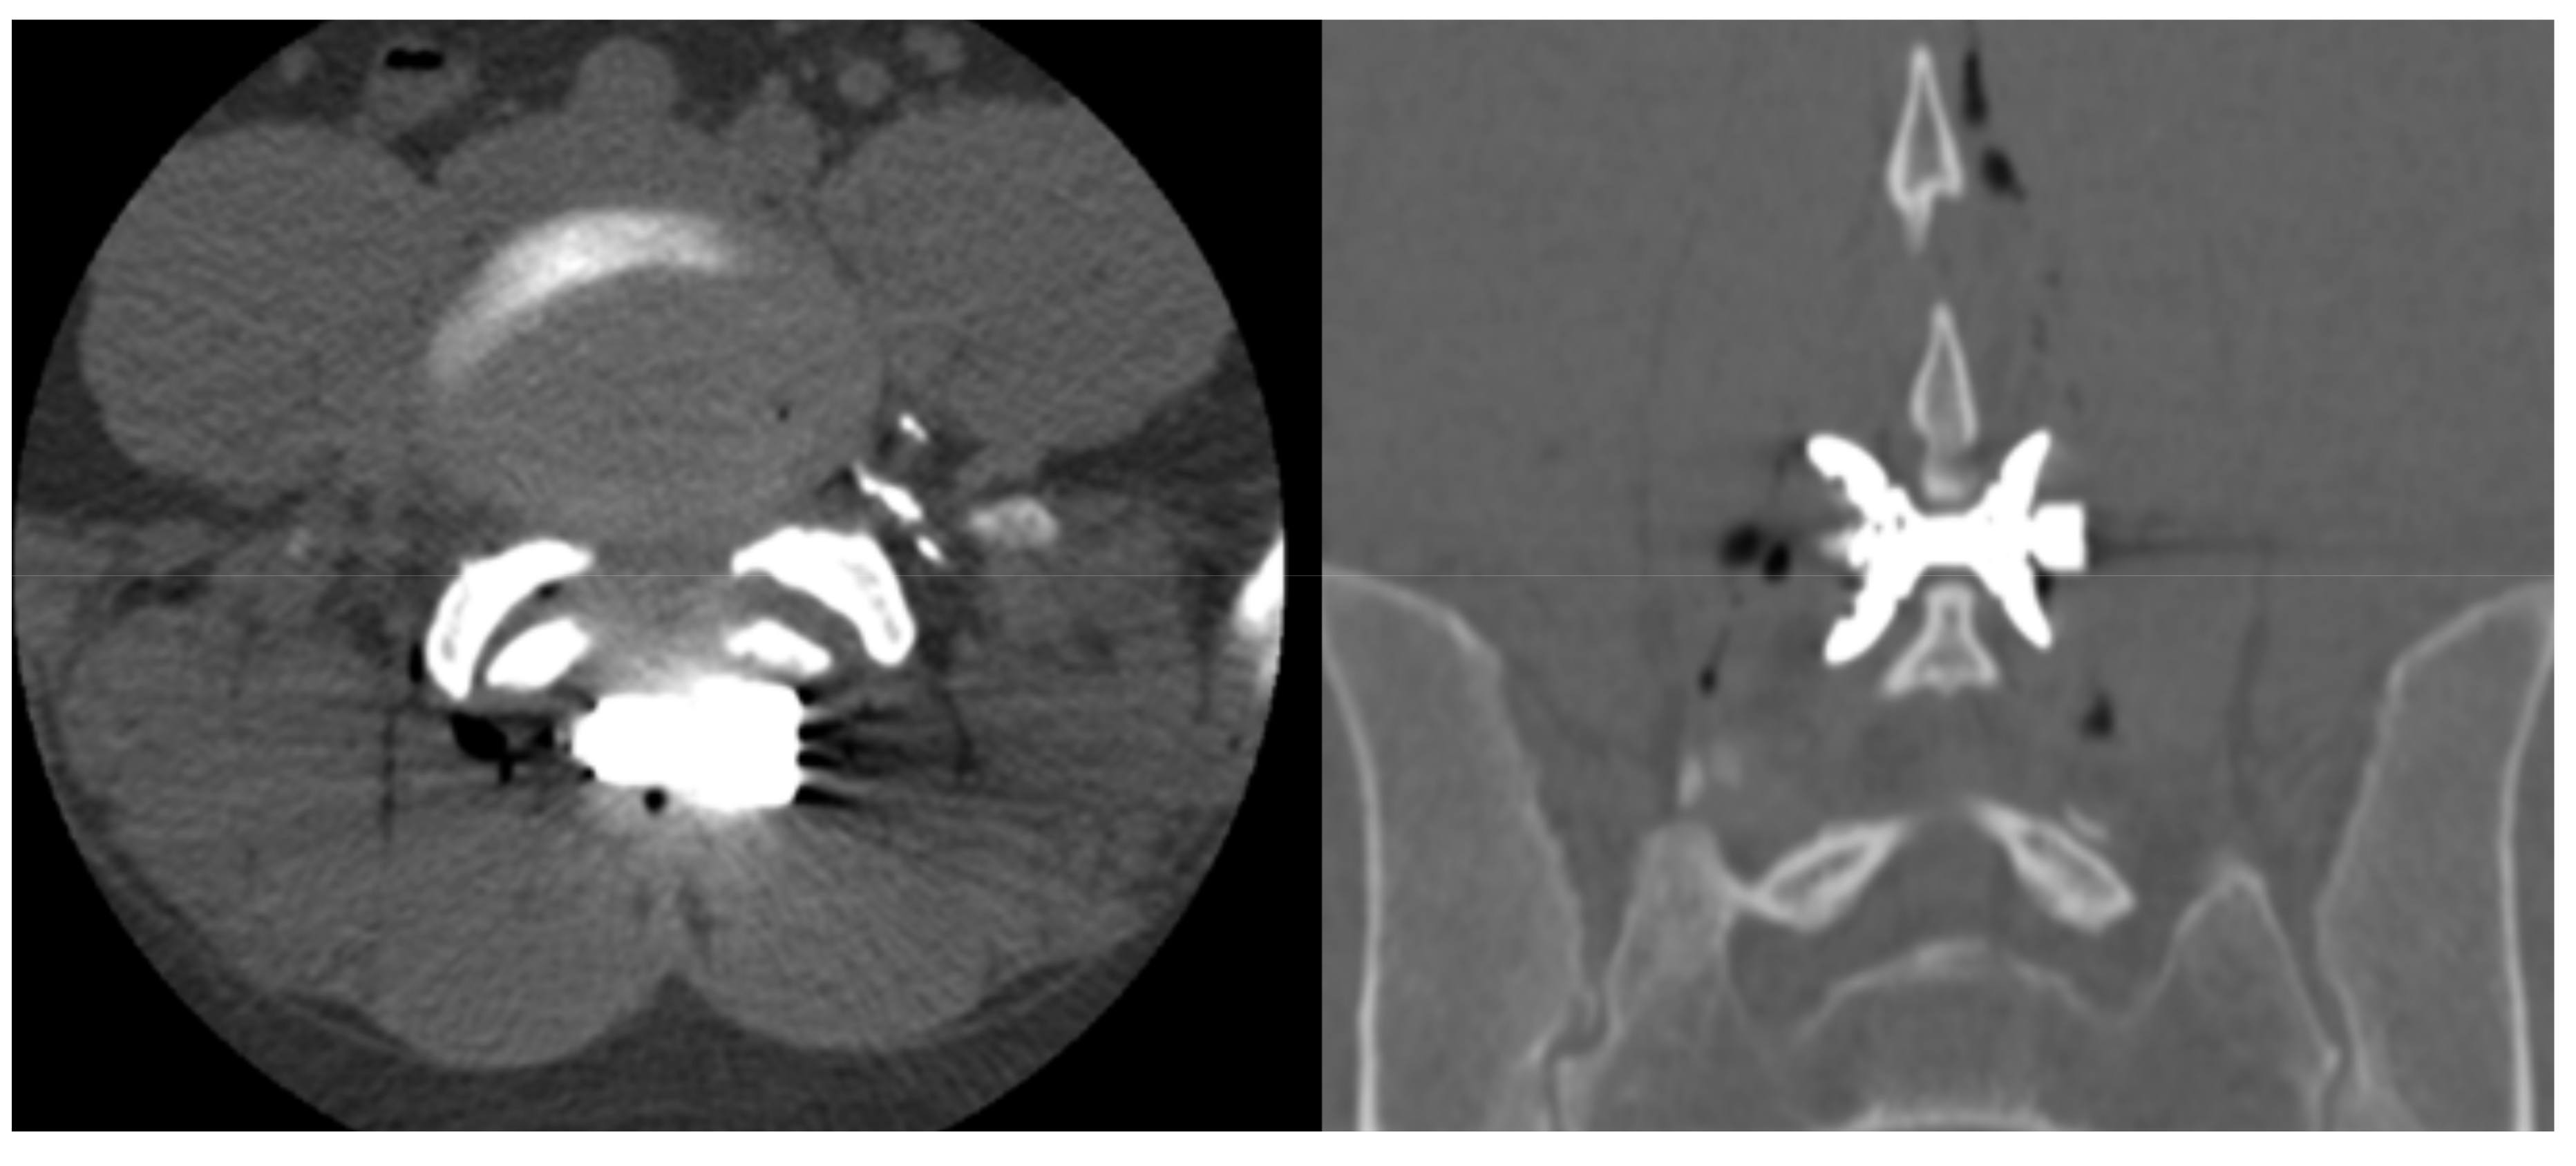

- Bonaldi, G.; Bertolini, G.; Marrocu, A.; Cianfoni, A. Posterior vertebral arch cement augmentation (spinoplasty) to prevent fracture of spinous processes after interspinous spacer implant. AJNR Am. J. Neuroradiol. 2012, 33, 522–528. [Google Scholar] [CrossRef]

- Manfré, L. Posterior Arch Augmentation (Spinoplasty) before and after Single and Double Interspinous Spacer Introduction at the Same Level: Preventing and Treating the Failure? Interv Neuroradiol. 2014, 20, 626–631. [Google Scholar] [CrossRef]